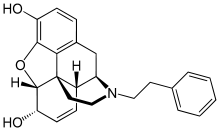

Opium alkaloids and derivatives

Phenanthrenes naturally occurring in (opium):